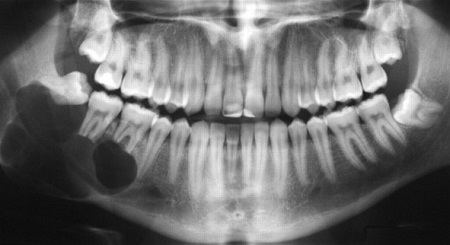

Vì hình ảnh 2D có thể bị giới hạn, không thể hiện rõ bên trong xương hàm, các góc khuất, chỗ dị tật,… các mô hình in 3D được sử dụng để hiểu sâu hơn về xương.

Trong phẫu thuật xương hàm, việc đo đạc, lên kế hoạch, chuẩn bị sẵn xương thay thế từ xương mác là cực kỳ quan trọng. Việc chuẩn bị này cần có mô hình xương hàm 3D chính xác.

Xương hàm được in từ máy in 3D: Phần xương bên trái của bệnh nhân đã bị rỗng, cần thay thế